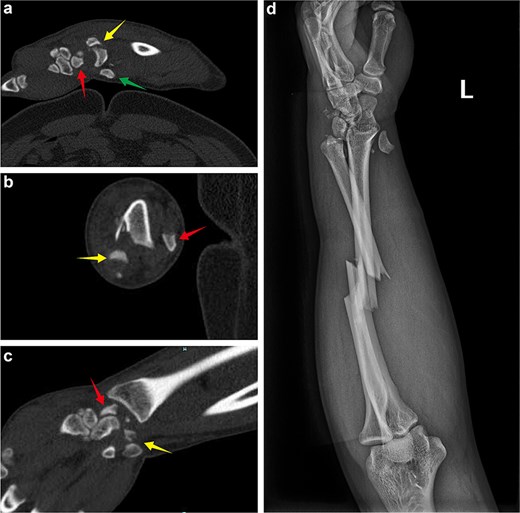

A 45-year-old manual worker presented following a fall from a scaffold about 2 m high. On examination, significant swelling of the left forearm and wrist was noted, with the disappearance of arterial pulsation and pallor of the hand. The patient also reported progressive paresthesia in the left hand, and motor weakness was observed. Emergency X-ray and wrist computed tomography (CT) scans revealed fractures of the ulna and radius, a dorsal fracture of the distal radius with dislocation of the inferior radioulnar joint, and dorsal dislocation of the lunate bone. Additionally, a scaphoid fracture, partially displaced toward the volar side was noted, along with a concomitant triquetrum fracture (Fig. 1). An emergency wound debridement and decompression procedure was performed. During the surgical intervention, a lazy S-shaped incision, ~25.0 cm in length, was made on the left palm and the palmar side of the forearm. Fasciotomy was conducted to release the deep fascia (Fig. 2). Intraoperatively, the wrist joint capsule was found to be damaged, exposing a scaphoid fracture that had fragmented into two pieces, with one fragment displaced toward the volar side. Additionally, the triquetrum bone was fractured into two pieces, with one fragment displaced toward the radius (Fig. 2). Following fracture reduction, the volar fragment of the scaphoid fracture was fixed in conjunction with the triquetrum fracture fragment using two Kirschner wires. The radial-carpal joint was also stabilized with two K-wires. Postoperative X-ray images revealed a poor reduction of the fracture ends, while the position of the lunate bone was generally considered acceptable (Fig. 3).

(a) Emergency admission sagittal CT of the wrist showing the dorsal dislocation of the lunate, the fracture end of scaphoid bone in the wrist joint, and the volar displacement of the scaphoid bone. (b) Axial CT of the wrist showing the dorsal displacement of the lunate and the fracture end of the scaphoid bone. (c) Coronal CT of the wrist showing the fracture end of the scaphoid bone and the fracture end of the triquetrum bone. (d) Emergency admission X-ray revealing the dorsal dislocation of the lunate bone, volar displacement of the scaphoid fracture end, injury to the inferior radioulnar joint, and a middle radius-ulnar fracture.